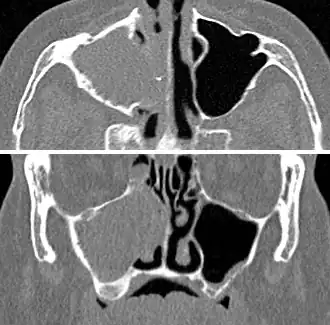

-

CT of chronic sinusitis -

CT scan of chronic sinusitis, showing a filled right maxillary sinus with sclerotic thickened bone -

For sinusitis lasting more than 12 weeks, a CT scan is recommended.[66] On a CT scan, acute sinus secretions have a radiodensity of 10 to 25 Hounsfield units (HU). In a more chronic state, they become more viscous, with a radiodensity of 30 to 60 HU.[69]